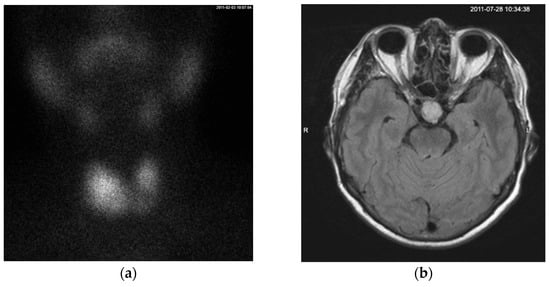

2. Case Presentation